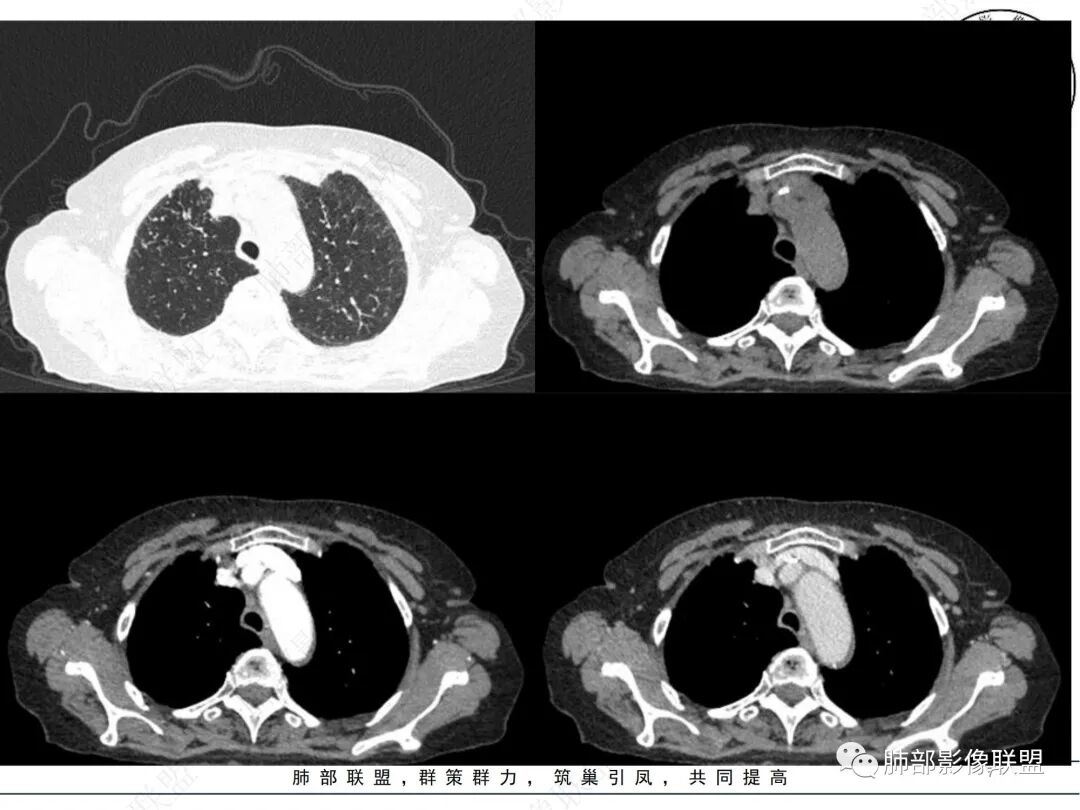

2. CT示右肺上叶多发斑片状实变影,结节影,集群散落,夹杂条索影,边界可分辨,有沿支气管血管束分布趋势,可见树芽征。病灶新旧不等、密度不均。右上叶支气管壁不均匀节段性增厚狹窄,斑点状钙化。纵隔旁部分肺组织含气不良,并显示轻度扩张支气管。病灶邻近胸膜增厚,轻度强化。

4.纵隔多发增大淋巴结,部分融合、钙化。

成簇分布斑片影、结节影、树芽征,边界较清楚,新旧不等,节段性支气管壁增厚伴钙化,管腔狭窄,纵隔及肺门淋巴结增大钙化等都较符合“继发性肺结核、支气管内膜结核”诊断。